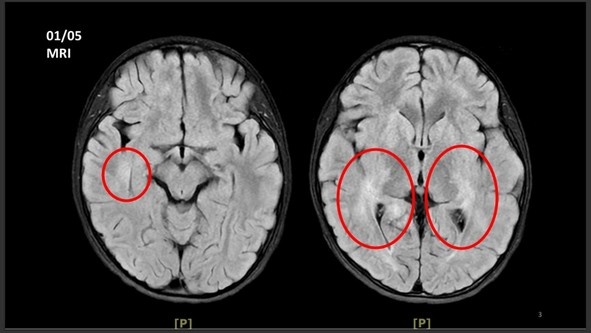

王傳育主任指出,女童當時血壓明顯偏高,心跳也較慢,醫療團隊擔心已有腦壓升高或顱內病變,立即安排住院,並同步給予降低腦壓治療與核磁共振掃描。檢查結果顯示,小腦、視丘及大腦白質、皮質下都可見異常訊號,符合急性散播性腦脊髓炎的影像表現。

左圖:王傳育主任說,檢查結果顯示,女童小腦、視丘及大腦白質、皮質下都可見異常訊號,符合急性散播性腦脊髓炎的影像表現。